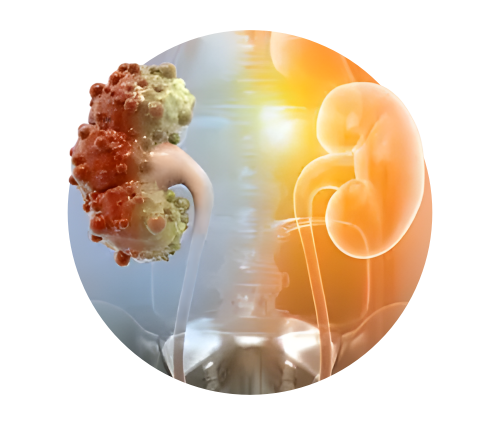

Kidney / Renal Transplantation

Advanced Care for End-Stage Kidney Disease

A kidney transplant is the most effective long-term treatment for patients with End-Stage Renal Disease (ESRD) or Chronic Kidney Disease (CKD Stage 5). It offers better survival, improved quality of life, and greater freedom compared to lifelong dialysis.